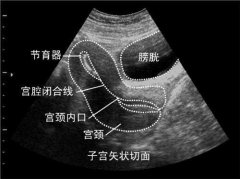

B超機